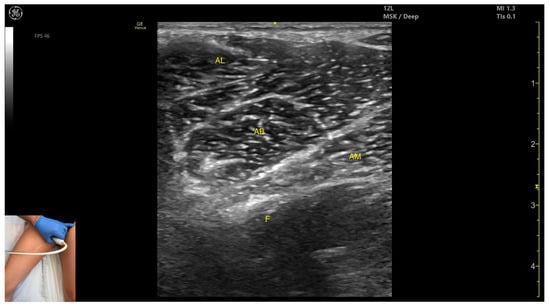

3.7. Adductor Longus (AL)

3.7.1. Overview

3.7.2. Ultrasound Identification

3.7.3. Key Ultrasound Landmarks

- Muscle position: It is the most superficial muscle mass at this level. Lateral to it lies the sartorius muscle, and medially, the gracilis muscle. The adductor canal is also visualized laterally.

- External fascia: It presents a pronounced fascia that separates it from the adductor magnus, adductor brevis, sartorius, and gracilis muscles during botulinum toxin injection.

- Dynamic evaluation: During dynamic evaluation, scanning proximally toward the hip joint, the adductor brevis, which lies deep to the adductor longus, becomes more prominent. Scanning distally toward the distal third of the medial thigh, the adductor longus gradually decreases in thickness until it disappears from view, at which point the gracilis and sartorius muscles become adjacent (Video S2). Contraction is visible during hip adduction and internal rotation maneuvers.

3.8. Adductor Magnus (AM)

3.8.1. Overview

3.8.2. Ultrasound Identification

3.8.3. Key Ultrasound Landmarks

- Muscle morphology: It is the largest and deepest muscle of the adductor group.

- Muscle position: It is the first muscle mass superficial to the femoral cortex at this level. It is covered superficially by the gracilis muscle; medial to it lies the semimembranosus.

- External fascia: It has a well-defined fascia separating it from the gracilis and semimembranosus, supporting safe BoNT-A injections.

- Dynamic evaluation: During dynamic evaluation, scanning distally toward the knee joint, a reduction in muscle bulk is observed in both the AM and gracilis. Muscle contraction is visible during hip adduction and hip flexion maneuvers.